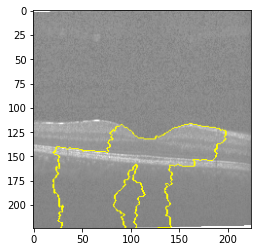

Fig 6, 7, 8 and 9 depicts the visualization of correct predictions by our proposed CNN model where fig 6 is class CNV, fig 8 is class DME, fig 7 is DRUSEN and finally, fig 9 is NORMAL. Here the first photo in every class is the original image. The LIME map of our suggested model’s prediction is shown in image B whereas in image C the positive region is highlighted in specific sections on the original image. For Image D we have increased the number of features from 5 to 10 thus more regions have been predicted as the positive region which is highlighted in green. After increasing the features from 5 to 10, some of the regions are predicted wrongly. The red regions represent the output of incorrect prediction. The following image represents the Grad-CAM heatmap highlighting the regions with our model’s prediction.